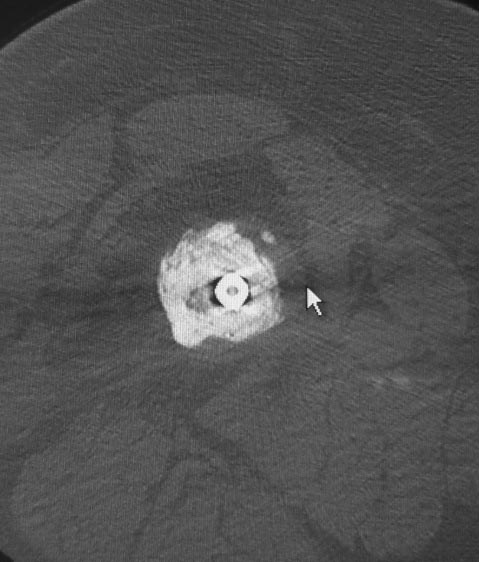

Уважаемые коллеги. Хотелось бы выслушать мнения и советы по представленному случаю. Пациент 42 лет, вес 130 кг, рост около 160 см, сахарный диабет в легкой форме (впервые выявлен после травмы). Травма в феврале 2011 г. - упал с мотоцикла на отдыхе за рубежом. По возвращении в Россию был прооперирован в несколько этапов: в марте 2011 г. - остеосинтез обеих костей правого предплечья пластинами по поводу открытого перелома; интрамедуллярный остеосинтез правого бедра; остеосинтез проксимального конца правой большеберцовой кости. В апреле 2011 г. был доставлен 1 блокирующий винт в дистальное отверстие гвоздя и выполнена пластика крестообразных и наружной боковой связок левого коленного сустава. В феврале 2012 г. были удалены фиксаторы с проксимального конца правой большеберцовой кости и выполнена пластика крестообразных и наружной боковой связок правого коленного сустава. За это время пациент смог начать ходить, сначала с костылями, а затем - без дополнительной опоры. Летом 2013 г. решил укрепить ноги с помощью подъемов пешком на пятый этаж. В результате - усталостная рефрактура правого бедра и перелом интрамедуллярного гвоздя. 09.09.2013 - реостеосинтез латеральным бедренным гвоздем с пластикой костной аутостружкой + СhronoS. Сейчас, через 6 мес после операции, может ходить без дополнительной опоры, периодически беспокоит болезненность в области правого бедра. На сегодняшних КТ - отсутствие признаков консолидации. Нужно ли что то делать и, если да, то что? Рассматриваемые варианты: повторная костная пластика дефекта; доставить блокирующие винты (самый проксимальный винт был удален через 3 мес после операции). Еще раз менять гвоздь не хотелось бы. На представленных снимках: бедро в 2011 г., через несколько мес после операции; в 2012 г., на стадии консолидации; со сломанным гвоздем; сразу после повторной операции (3 рентгенограммы). Все КТ - сегодняшние. Заранее спасибо за ответы.

ждать-не ждать? Срочности нет, подождать можно, но активно, т.е. оценить клиническую и рентгенологическую динамику: два месяца назад, сейчас и еще через пару месяцев. Уменьшатся боли, появится более убедительная мозоль - ждите и наблюдайте дальше. Отсутствие положительной динамики можно приравнять к отрицательной динамике. Очевидно, что здесь имеют место быть обе проблемы: биологическая -мозоль слабая и механическая - тонкий гвоздь, недостаточная стабильность. Тогда -удаление, рассверливание (очень аккуратное, по 0.5 мм шаг, острыми фрезами, чтобы не пожечь кость - кортикал толстый и довольно прочный). Для 130 кг диаметр гвоздя минимум 12 мм, лучше больше. Здесь можно и 14мм гвоздь взять и блокировать дистально винтами 6,0 мм. Открывать перелом и пытаться делать еще пластику экстрамедуллярно не стоит. Рассверливания будет достаточно.

Источник проблем - отсуствие рассверливания, тонкий гвоздь и костная пластика. При интрамедуллярном остеосинтезе (относительная стабильность) класть кусочки кости открыто бесполезно - не приживут. Только еще ухудшили кровоснабжение концов. А что там с длиной сегмента? Если длина не потерялась - реостеосинтез с рассверливанием, как А.Семенистый написал. Если укорочение - удалить, остеотомия на другом уровне и дистракиця, на стыке - компрессия, и по достижении нужной длины - заштифтовать с рассверливанием, аппарат снять только после запирания гвоздя.

Боли в области ложного сустава подтверждают, что ожидания не помогут и приведут к повторному перелому интрамедуллярного гвоздя. Стандартная процедура - рассверливание и толстый гвоздь в динамике. Нагрузка с первых дней.

По представленным рентгенограммам проведенный остеосинтез был стабильным. К.Т.указывает об отсутствии развития признаков мозолеобразования. Стоит подумать об установлении причин несращения в питании, одной из причин может быть дефицит аминокислотных фракции белков, витаминов и минералов.